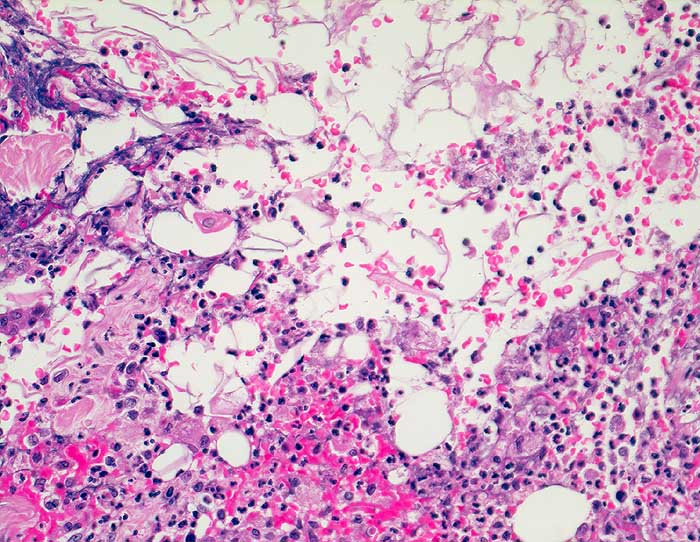

Entzündlich veränderte Epidermoidzyste

Epidermal ausgekleidete Zysten (Atherome) werden oft punktiert. Pathognomonisch sind dichte Zusammenballungen von kernlosen gelb gefärbten Hornschuppen. Nach einer Zystenruptur ist der Hintergrund detritisch und enthält wie bei einem Abszess zahlreiche neutrophile Granulozyten und Schaumzellen. Die Hornschuppen werden oft von Fremdkörperriesenzellen und Histiozyten umlagert. Nekrotische Lymphknotenmetastasen von hochdifferenzierten Plattenepithelkarzinomen können ähnlich aussehen. Die Plattenepithelzellen des Karzinoms sind aber oft bizarr geformt und weisen atypische Kerne auf.